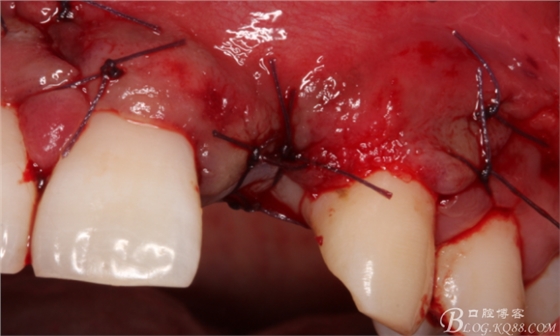

保留齦乳頭翻小瓣。

翻開后驚喜的發(fā)現(xiàn),術(shù)區(qū)成骨非常好,去除部分骨才暴露那顆長鈦釘。

取出影響種植入路的長鈦釘。

擴(kuò)孔。

骨擠壓。

植入植體。

縫合。